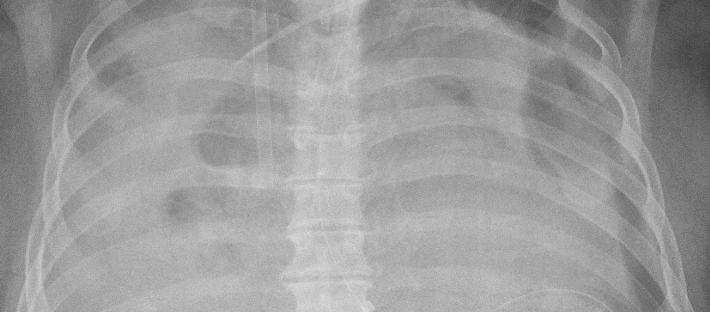

Lindèn et al på Karolinska sjukhustet har studer lungemorfologi og -funksjon i 21 pasienter etter ECMO for alvorlig ARDS (3). De finner mindre lungemorfologiske forandringer enn i andre studier med konvensjonell behandling for ARDS, men mengden av forandringer korrelerer med varigheten av ECMO-behandlingen. Lungefunksjonen og fysisk funksjon post-ECMO var i nedre normalområde, med mer uttalt reduksjon jo lenger pasientene hadde ligget på ECMO. De er antatt at denne sammenhengen reflekterer økende alvorlighetsgrad av den underliggende sykdommen. Pasientene rapporterte subjektive respirasjonsproblemer post-ECMO, men i mindre grad enn i andre studier med konvensjonell ARDS-behandling.